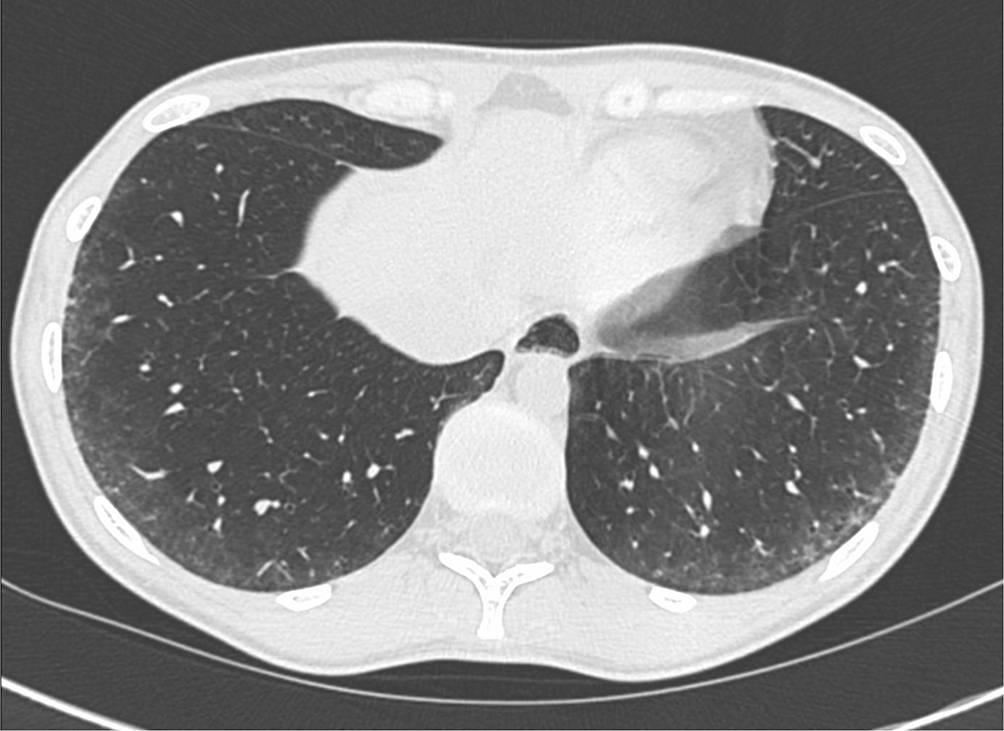

Als Folge der fibrosierenden Veränderungen bei der NSIP finden sich auch ein Volumenverlust der Lunge, eine irreversible Erweiterung von Bronchien (Bronchiektasien) und bei manchen PatientInnen auch ein gering ausgeprägtes Honigwabenmuster (Honeycombing, [8, 10]). Als Honeycombing beschreibt man eine Anhäufung (Cluster) von zahlreichen aneinander grenzenden Zysten ähnlicher Größe, die sich die Wände teilen ([42]; Abb. 2).

Abb. 2

CT einer 32 Jahre alten Patientin mit einer bekannten Sklerodermie. Die CT zeigt mehrreihige zystische Veränderungen in der Peripherie beider Unterlappen (Honeycombing) im Sinne eines sog. UIP(„usual interstitial pneumonia“)-Musters

Deutlich seltener (10 %) findet sich bei PatientInnen mit SSc-ILD das Muster „usual interstitial pneumonia“ (UIP), welches durch retikuläre Verdichtungen, Traktionsbronchiektasien und Honeycombing in basaler und subpleuraler Verteilung gekennzeichnet ist [8, 10]. Bei weiteren 10 % der PatientInnen finden sich Zeichen einer fibrosierenden Lungenerkrankung, die keinem definierten Muster zugeordnet werden können.